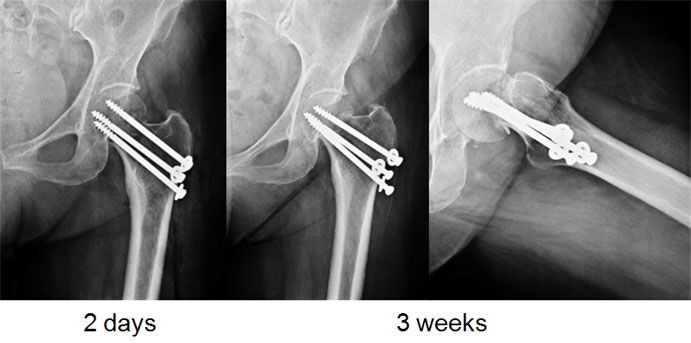

| 3 months post surgery |

In her sleep one day she suddenly felt a sudden sharp pain in the hip joint, afterwards she was ok, so she continued to walk on the leg. She came back to us after a few days of limping and not being able to walk as earlier. The x-rays at that time showed this picture – where the screws had cut out of the ball (femoral head) and were even pinching on the socket. This was the cause of her pain, limp & shortening. |